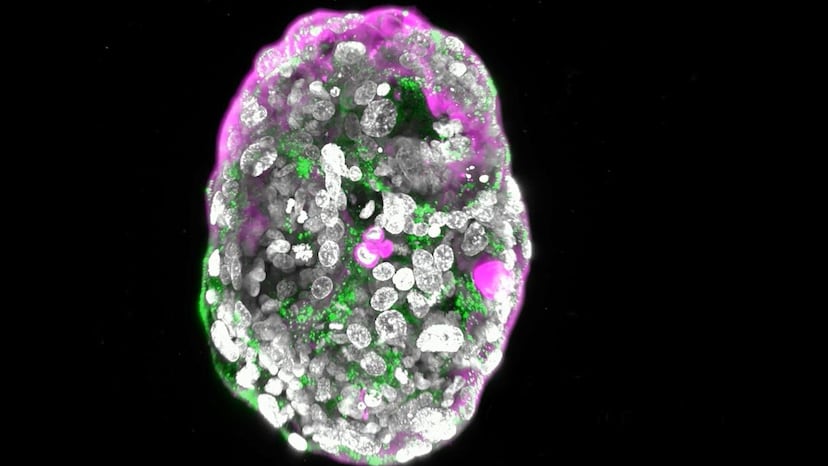

Modelo de embrión humano (a los ocho días) creado en el laboratorio del científico palestino Jacob Hanna, del Instituto Weizmann de Ciencias.Foto: INSTITUTO WEIZMANN DE CIENCIAS | Vídeo: INSTITUTO WEIZMANN DE CIENCIAS

El embriólogo británico Lewis Wolpert (1929-2021) dejó una frase legendaria: “El momento más importante de tu vida no es tu nacimiento, ni tu matrimonio, ni tu muerte, sino la gastrulación”. Exactamente, 14 días después de que un espermatozoide y un óvulo se unan, el embrión, una diminuta esfera de unos cientos de células, iniciará la gastrulación, un proceso de una semana en el que esa pelotita se transformará en el primer boceto del individuo. Esos días son el mayor enigma de la formación de un ser humano, a causa de las barreras técnicas y éticas para investigarlos. El científico palestino Jacob Hanna, uno de los líderes mundiales de este campo, ha logrado crear un nuevo modelo de embrión humano, obtenido a partir de células madre, que imita la arquitectura tridimensional de un embrión natural de entre 7 y 14 días, según sus resultados preliminares, a los que ha tenido acceso EL PAÍS. “Es la primera vez que se obtienen embriones humanos sintéticos sin modificaciones genéticas”, afirma Hanna, del Instituto Weizmann de Ciencias, en Rejovot (Israel). El borrador de su estudio se ha publicado posteriormente en el repositorio bioRxiv.

Las células de un embrión de pocos días son pluripotentes: pueden transformarse en cualquier célula de una persona adulta, ya sea del corazón, del pulmón o del cerebro. Esas células todopoderosas también se pueden extraer y cultivar individualmente en el laboratorio. Se dividirán y crearán copias idénticas de sí mismas por un tiempo indefinido. El grupo de Jacob Hanna utiliza un cóctel químico para inducir la autoorganización de células madre embrionarias en una estructura similar a un embrión humano.